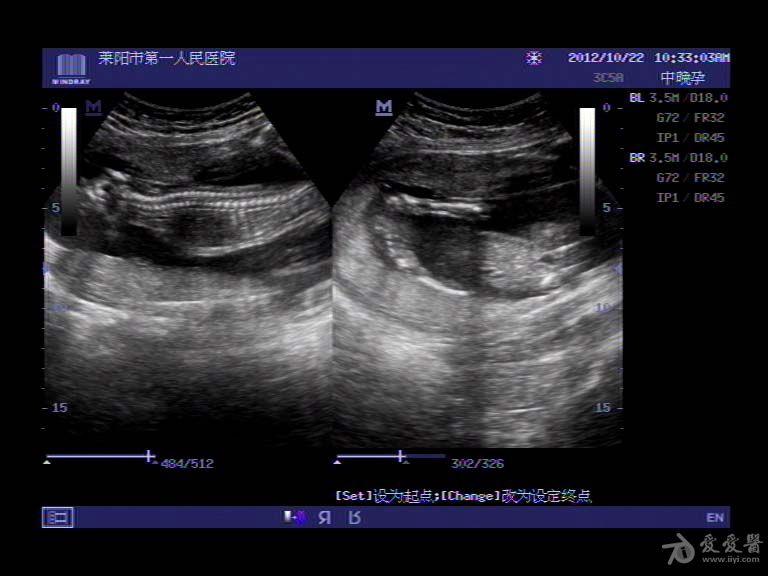

无脑儿超声

无脑儿

一无脑儿b超图片